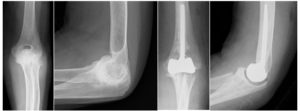

人工肘関節

人工肘関節1

リウマチ肘による痛みと可動域制限に対して、人工肘関節置換術を施行、痛みなく可動域も良好です。

人工肘関節2

肘関節骨折に対し他院で手術を受けられましたが、肘の痛みと運動制限が残存し人工肘関節置換術を施行しました。痛みは消失し、可動域もほぼ正常に回復されました。